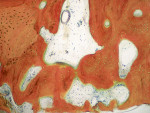

At 6 months, the site was re-entered with a full-thickness flap revealing full height and width preservation. A crestal sinus elevation was performed using the Versah drilling system (Figure 16),37,51 which is designed to increase bone-to-implant contact around the implant.52 The sinus membrane was elevated with the same graft mixture as placed in the initial socket defect. An implant (Tapered Pro, BioHorizons) was inserted into the osteotomy, a healing abutment was placed, and some of the remaining graft material was placed around it to support the papillae. The area was sutured and allowed to heal for 4 months prior to restoration. Clinically, the bone, keratinized tissue volumes, and size and shape of tooth No. 14 blended well with the adjacent teeth (Figure 17). Radiographic analysis showed excellent bone volume retention and remodeling in all areas it was placed (Figure 18). Histologic analysis showed a combination of new bone with osteoid and more mature bone (Figure 19). The core was 63% bone by volume, all vital in an area that has been reported as the weakest bone in the jaw and associated with high implant failure rates.53